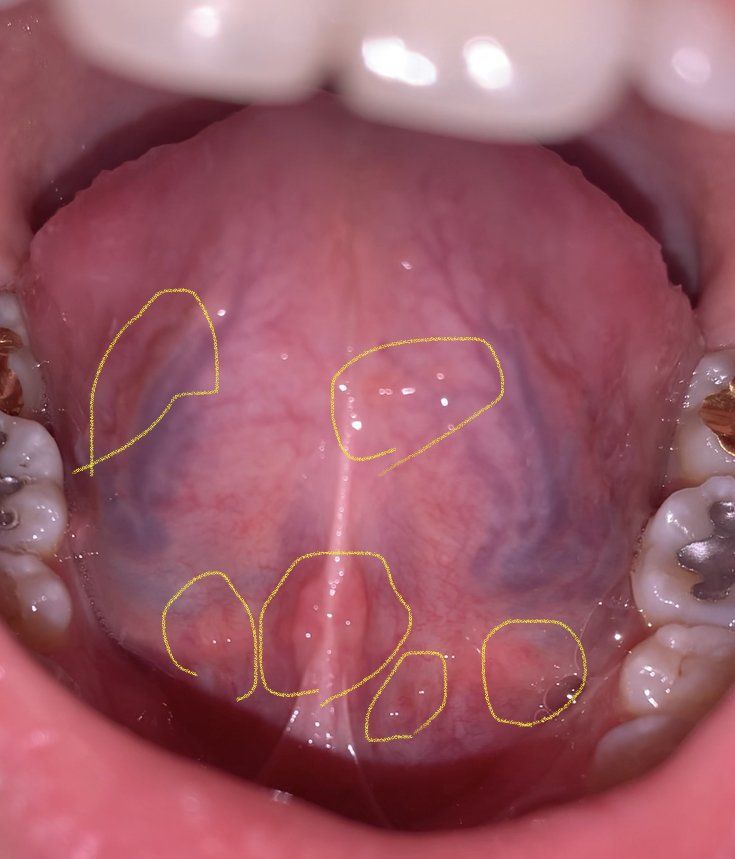

혀의 염증이 너무 많은데 심각한 건가요??

옛날부터 작은 염증? 수포?? 같은 것들이 있긴 했는데 점점 늘어나는 거 같아서 걱정입니다 ㅜㅜ 심각한 경우는 아니겠죠?? 통증은 전혀 없습니다 만약 치료가 필요한 경우면 치과로 가면 될까요??

정상적인 혀 상태로 보입니다. 작은 방울 같은 것은 육아조직으로 다른 이상이 있는 것은 아닙니다.

가운데 있는 것은 침이 나오는 구멍(설하선 입구)으로 약간 돌출되어 보입니다.

사진으로 보이는것은 혀아래 있는 정맥혈입니다. 정상적인 혀의 구조물로 염증이 생기거나 한것은 아닌것으로 보여요.

구강내에 음압을 형성하는습관이 있는 경우에는 혀나 혀의 아래 부위의 연조직이 자극을 받아서 돌출되는 경우가 있습니다.

불편감이나 통증이 있나요? 정상적인 구조물일 가능성이 있습니다. 나이가 들면서 조직이 조금씩 변화하면 주변 근육이나 조직이 튀어나오거나 보일 수 있습니다. 해당 사진으로는 그러한 것들이 의심됩니다. 표시해주신 부위에 특별히 발적,염증 등이 보이지 않고 흔히 치과에서 보이는 구강구조물 중 하나로 여겨집니다. 물론 정확한 것은 치과 방문 후 직접 평가를 받아보셔야 합니다.